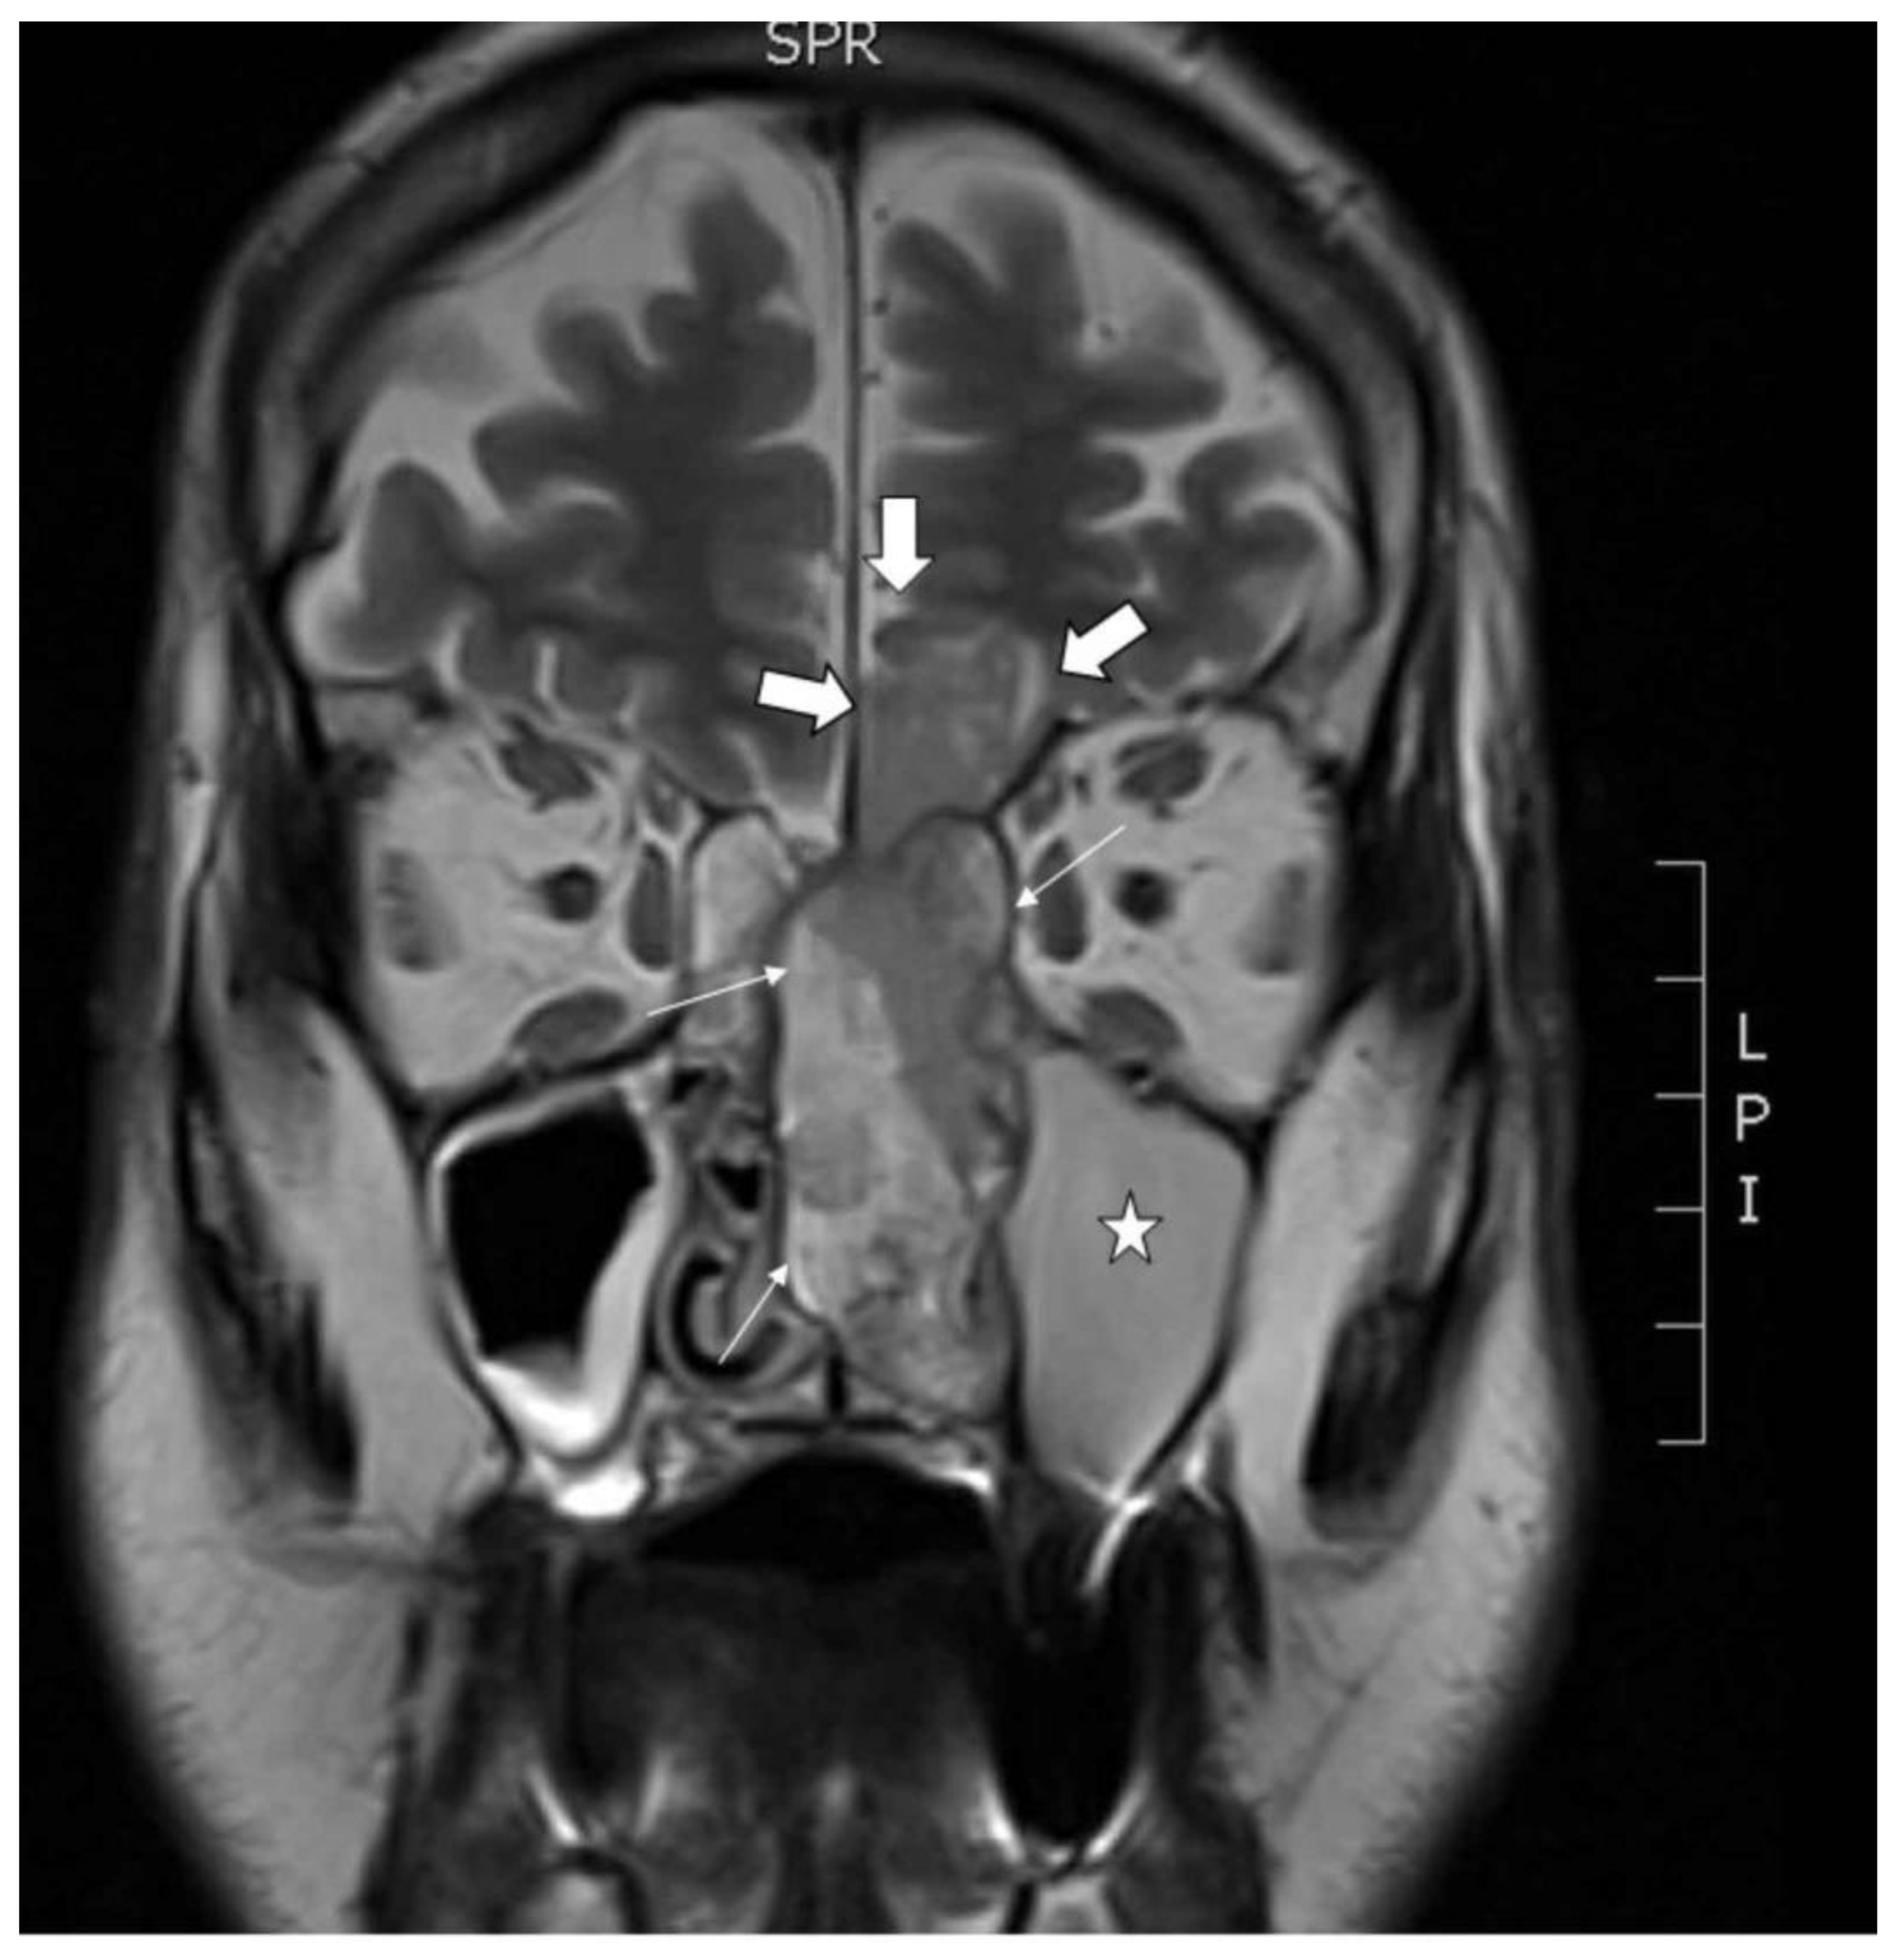

2.1. Clinical Description